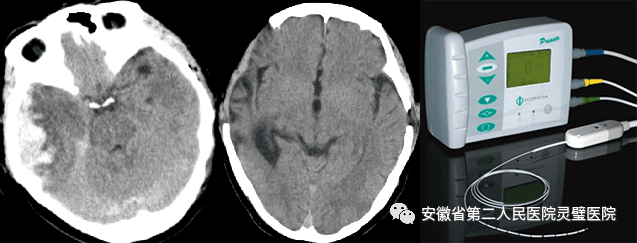

颅脑创伤是神经外科常见病、多发病,近十年来,我们成功诊治了大量重型颅脑损伤患者,尤其在特重型颅脑损伤、原发性脑干伤、弥漫性轴索损伤等方面积累了丰富的经验,并形成了以“神经多模态监测、亚低温治疗、镇静镇痛、大骨瓣减压以及精准化脑保护”等核心技术为特色的一体化标准化救治方案,重型颅脑创伤患者死亡率逐年降低,达到国内一流水平。

硬膜下血肿、脑挫裂伤术前和术后 颅内压监测